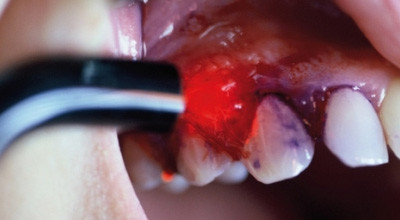

Mithilfe der digitalen Pulstechnik ist auch mit dem Diodenlaser eine gute und schnelle Schnittführung erreichbar, die aufgrund der Absorption der Laserstrahlung für diese Wellenlänge im Hämoglobin von einer guten Blutstillung begleitet wird. Die Abbildungen 3 bis 6 zeigen exemplarisch den Einsatz des Diodenlasers als Hardlaser zur Entfernung eines Fibroms. Auch für den chirurgischen Eingriff am Lippenbändchen – wie in den Abbildungen 7 bis 9 dargestellt – findet er Verwendung. Besonders bei unseren jungen Patienten liegt der Vorteil neben der Kürze des Eingriffs in der geringeren Blutung, im Verzicht auf die Naht und damit dem zweiten Eingriff.

Durch sein gutes Absorptionsverhalten im dunklen Gewebe ist der Diodenlaser hervorragend geeignet, kleine Gewebsneubildungen zu entfernen (Abb. 10 und 11). Auch größere Eingriffe sind durchaus möglich, da sie problemlos in mehreren Einzelschritten durchgeführt werden können. Die Blutungsarmut bei solchen präprothetischen chirurgischen Maßnahmen ermöglicht dabei eine sofortige temporäre Versorgung (Abb. 12 und 13).